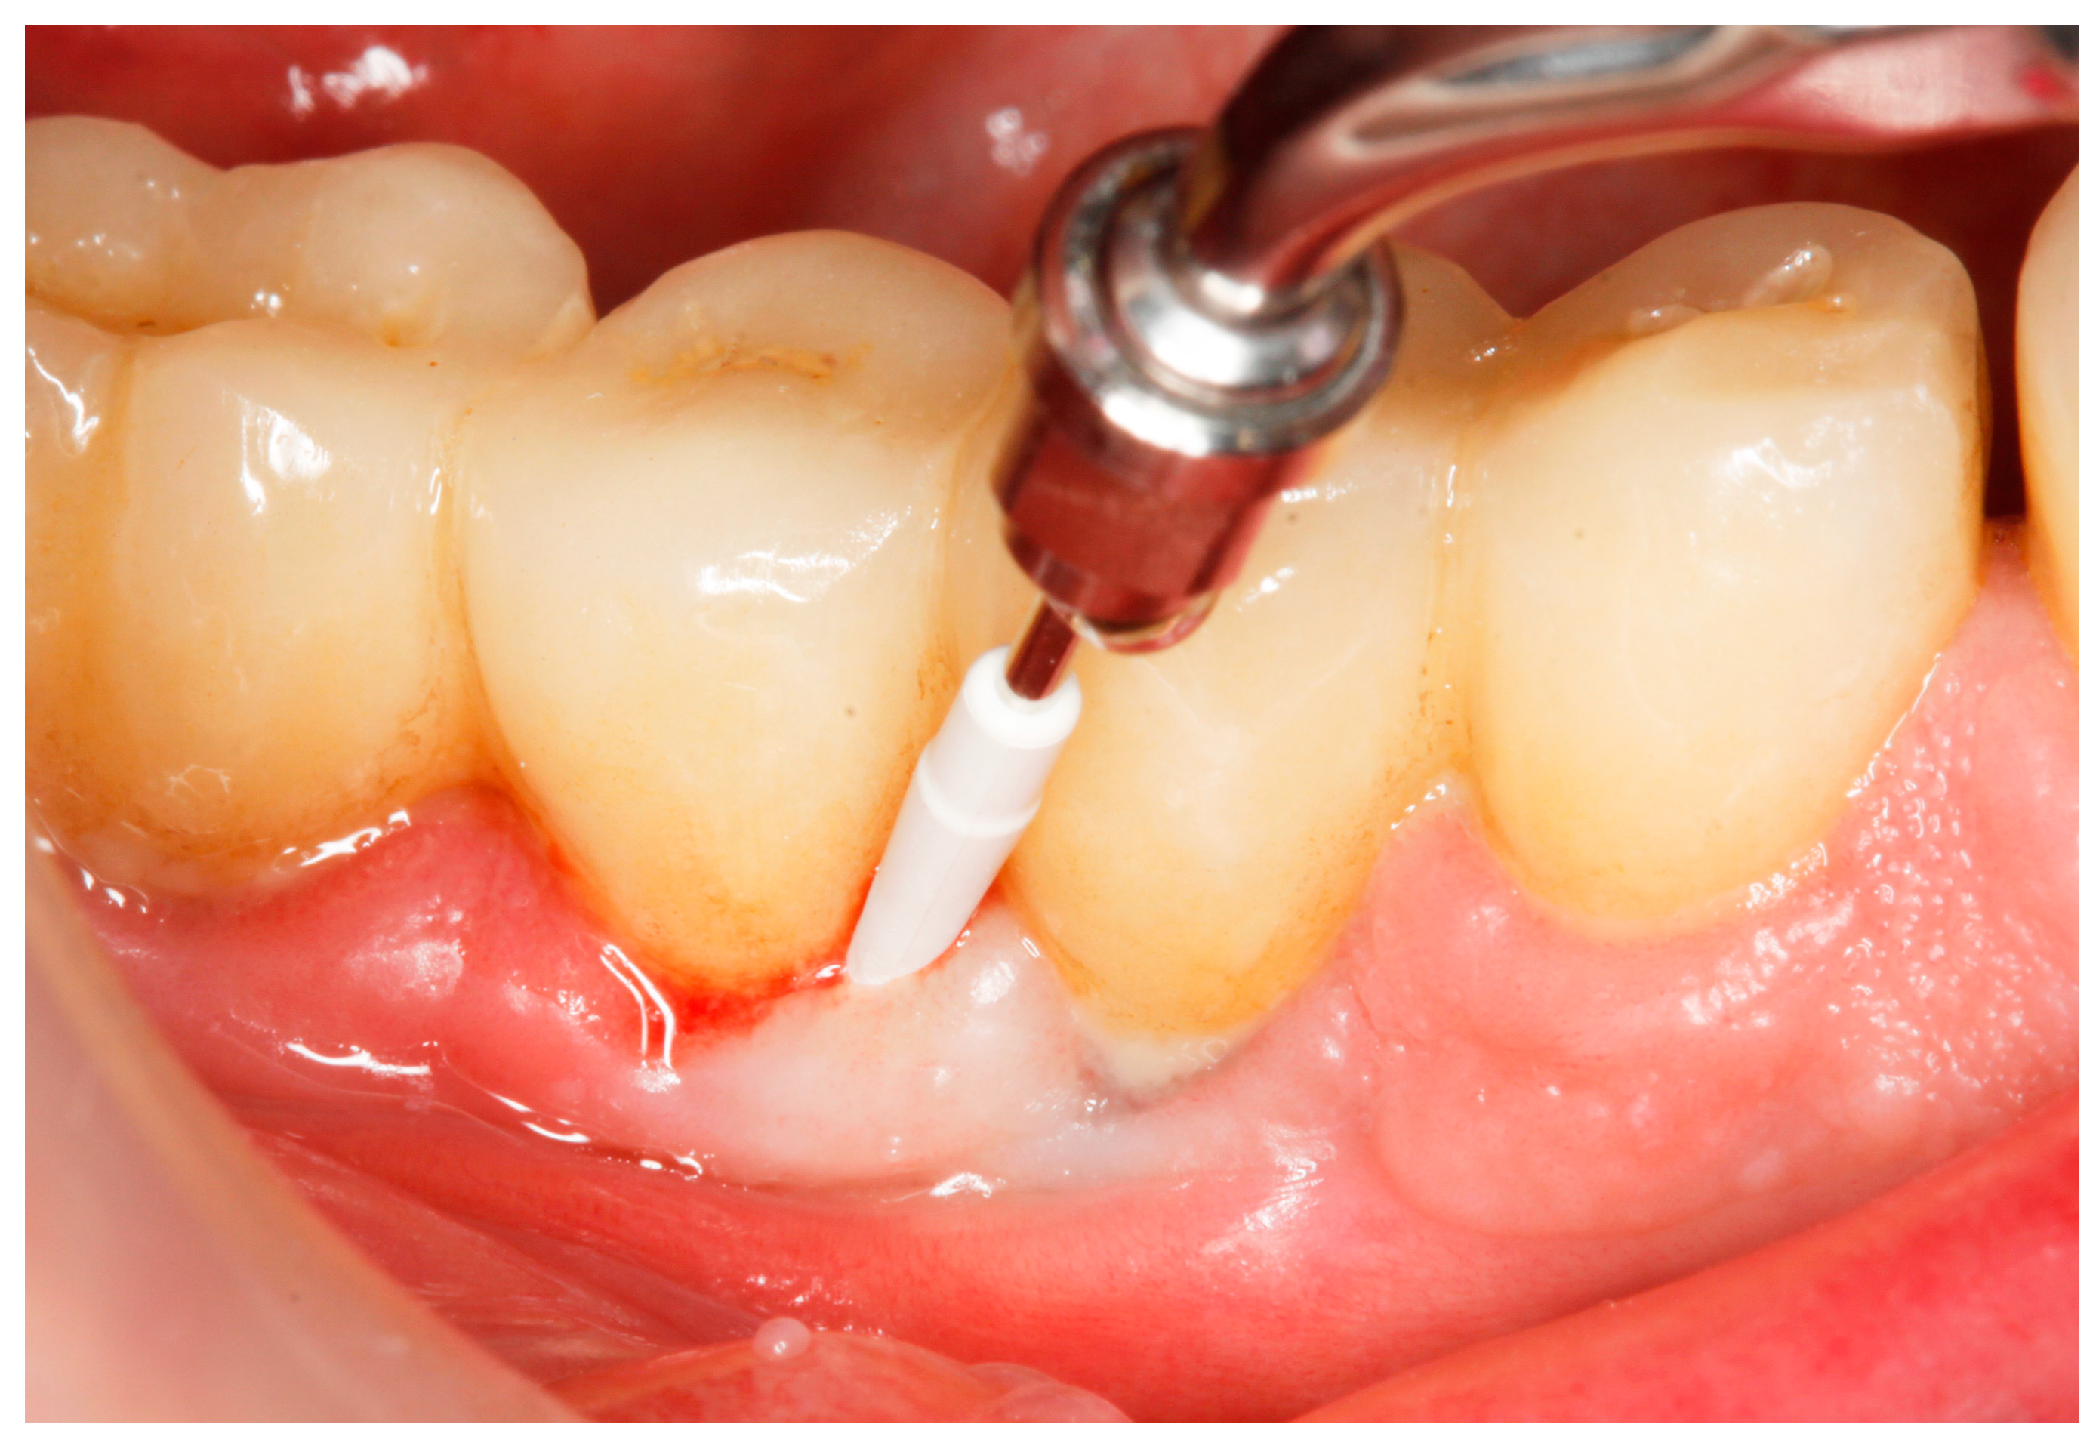

Baseline: Prior to PiM treatment, PMPR was performed in all subjects (Figure 3), for both teeth and implants. Each patient was assigned to one of the two treatment groups according to computer-generated randomization. One implant (the one with the greatest number of BoP points or the presence of a line of bleeding or profuse bleeding) with PiM in each patient was selected for the study. PMPR of the implants of interest was performed using an ultrasonic scaler with a plastic tip (Piezon® Master700 with Piezon® PI instrument, EMS, Nyon, Switzerland), and air polishing (Perioflow® handpiece, Airflow® PLUS powder, EMS, Nyon, Switzerland) was carried out at all sites. Piperacillin plus tazobactam gel Gelcide® (Italmed, Firenze, Italy) was prepared according to the manufacturer’s recommendations and was applied as follows: the solution was injected into the powder container, and the container was shaken until the solution became homogeneous. After mixing, the consistency of the mixture slightly increased, so it could be applied at the implant surface. Instrumentation was followed by subgingival application of the volatile mixture, depending on the patient’s group. For the Gelcide® group (test), topical application of Gelcide® was performed for the placebo group (control), topical application of a placebo (the volatile polymeric carrier alone) was carried out. The necessary quantity (not standardized) was then extracted from the mixed container with a syringe and inserted into the peri-implant sulcus at the apical extremity (Figure 4) until the excess became visible at the mucosal margin. Once the product had been applied, the excess was removed using a cotton ball.

Figure 3.

Mechanical debridement by means of an ultrasonic scaler with a plastic tip.